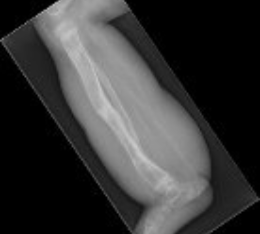

In children, correction of deformities due to developing cartilage can be accomplished in the following ways:

- Hemi-epiphysiodesis, with the use of small metal plates that are applied across the part of the bone which is still growing. This technique allows gradual guided correction of the deformity avoiding the need to break the bone (osteotomy).